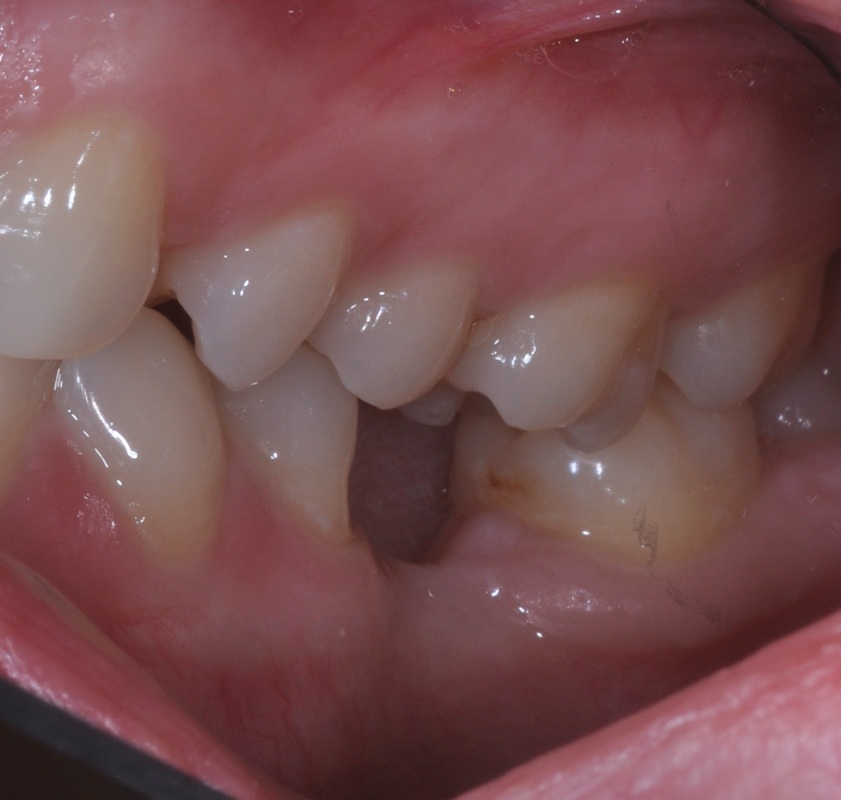

A 30 year old was concerned with the discomfort next to his impacted wisdom tooth and pain associated with cold and hot temperatures around the decayed back teeth.

After thorough dental examination Dr. Andrews recommended to extract the wisdom tooth (#17) and the second molar (#18) due to severe decay and poor prognosis for both teeth and to replace the second molar (#18) with a dental implant.

During only one 45-minute surgery both teeth were removed, a minor bone graft was placed and a wide-diameter (7 mm) dental implant was immediately inserted to replace the second molar. Four months later , #18 implant was restored with an all-ceramic crown.

Revolutionary digital scanning technology and CAD/CAM fabrication process had been used by Dr. Andrews to create an ideal emergence profile, ideal bite and natural anatomy for the crown.

Cavities on other teeth were treated with mercury-free, bio-mimetic white composite fillings.